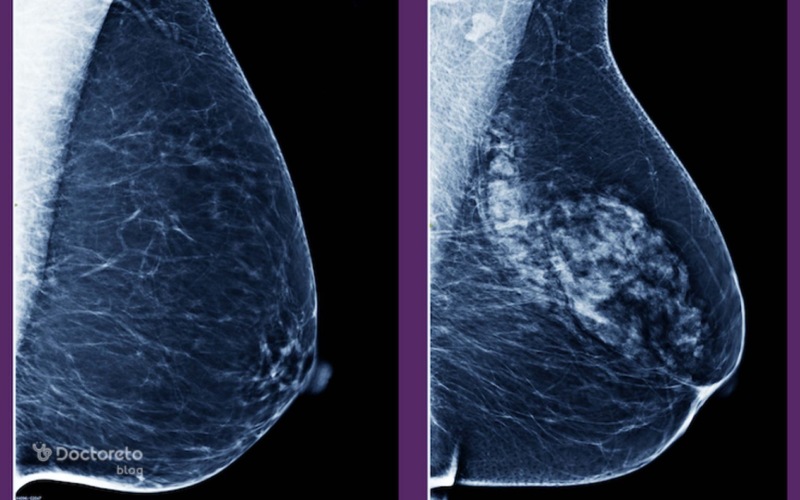

علائم سرطان سینه در زنان همیشه فقط یک توده مشخص و قابل لمس نیست و میتواند خود را با نشانههایی مانند تغییر شکل سینه، قرمزی یا پوست پرتقالی، تو رفتگی نوک سینه یا ترشح غیرطبیعی (خودبهخود، یکطرفه، تکمجرا) نشان دهد. گاهی فقط احساس سنگینی، سفتی در بخشی از سینه یا لمس غده زیر بغل میتواند هشداردهنده باشد. در این مطلب از دکترتو به زبان ساده علائم سرطان سینه در زنان با عکس آن را بررسی میکنیم و متوجه میشویم علائم دقیقا چه معنیای دارند و چه زمانی باید سریعتر به پزشک مراجعه کنید.

علائم سرطان سینه زنان با عکس در نواحی مختلف بدن

سرطان سینه ممکن است علاوه بر خود پستان، در نواحی دیگر هم علائم ایجاد کند، به خصوص زمانی که تومور به بافتهای اطراف یا اندامهای دیگر گسترش یافته باشد. درد یا تورم زیر بغل، استخواندردهای غیرقابل توضیح، سرفه مزمن، سردرد، کاهش وزن و خستگی شدید میتوانند نشانههای گسترش سرطان یا علائم عود سرطان سینه باشند. آگاهی از این علائم کمک میکند مراحل پیشرفته بیماری زودتر تشخیص داده شود.

توجه به علائم سرطان سینه در زنان با عکس آنها میتواند نقش مهمی در پیشگیری و درمان داشتهباشد. حتی اگر برخی از این علائم به دلیل مسائل غیرسرطانی باشد، نباید آنها را نادیده گرفت. به طور کلی، هرگونه تغییر در سینهها باید تحت نظر پزشک قرار گیرد. علاوه بر این، انجام معاینات خودآزمایی سینه به صورت ماهانه و مراجعه به پزشک برای ماموگرافی و دیگر تستهای تشخیصی میتواند به شناسایی زودهنگام این بیماری کمک کند. در نهایت با آگاهی از علائم و انجام اقدامات پیشگیرانه، میتوان خطرات ناشی از این بیماری را کاهش داد.